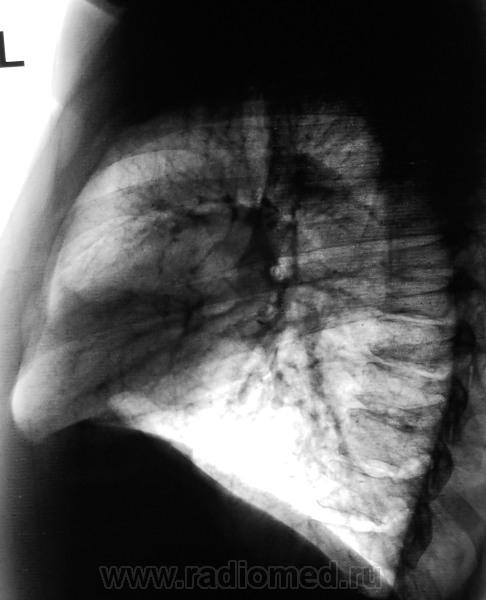

Уменьшение пневматизации нижней доли, плевро-медиастино-диафрагмальные спайки, деформация диафрагмы, средостения-больше данных за посттравматические изменения органов грудной клетки, + диафрагмальная грыжа.

Нарушение проходимости "среднедолевого или их?" бронха слева, гиповентиляция язычковых сегментов, тень в верхнем средостении. Центральный рак.